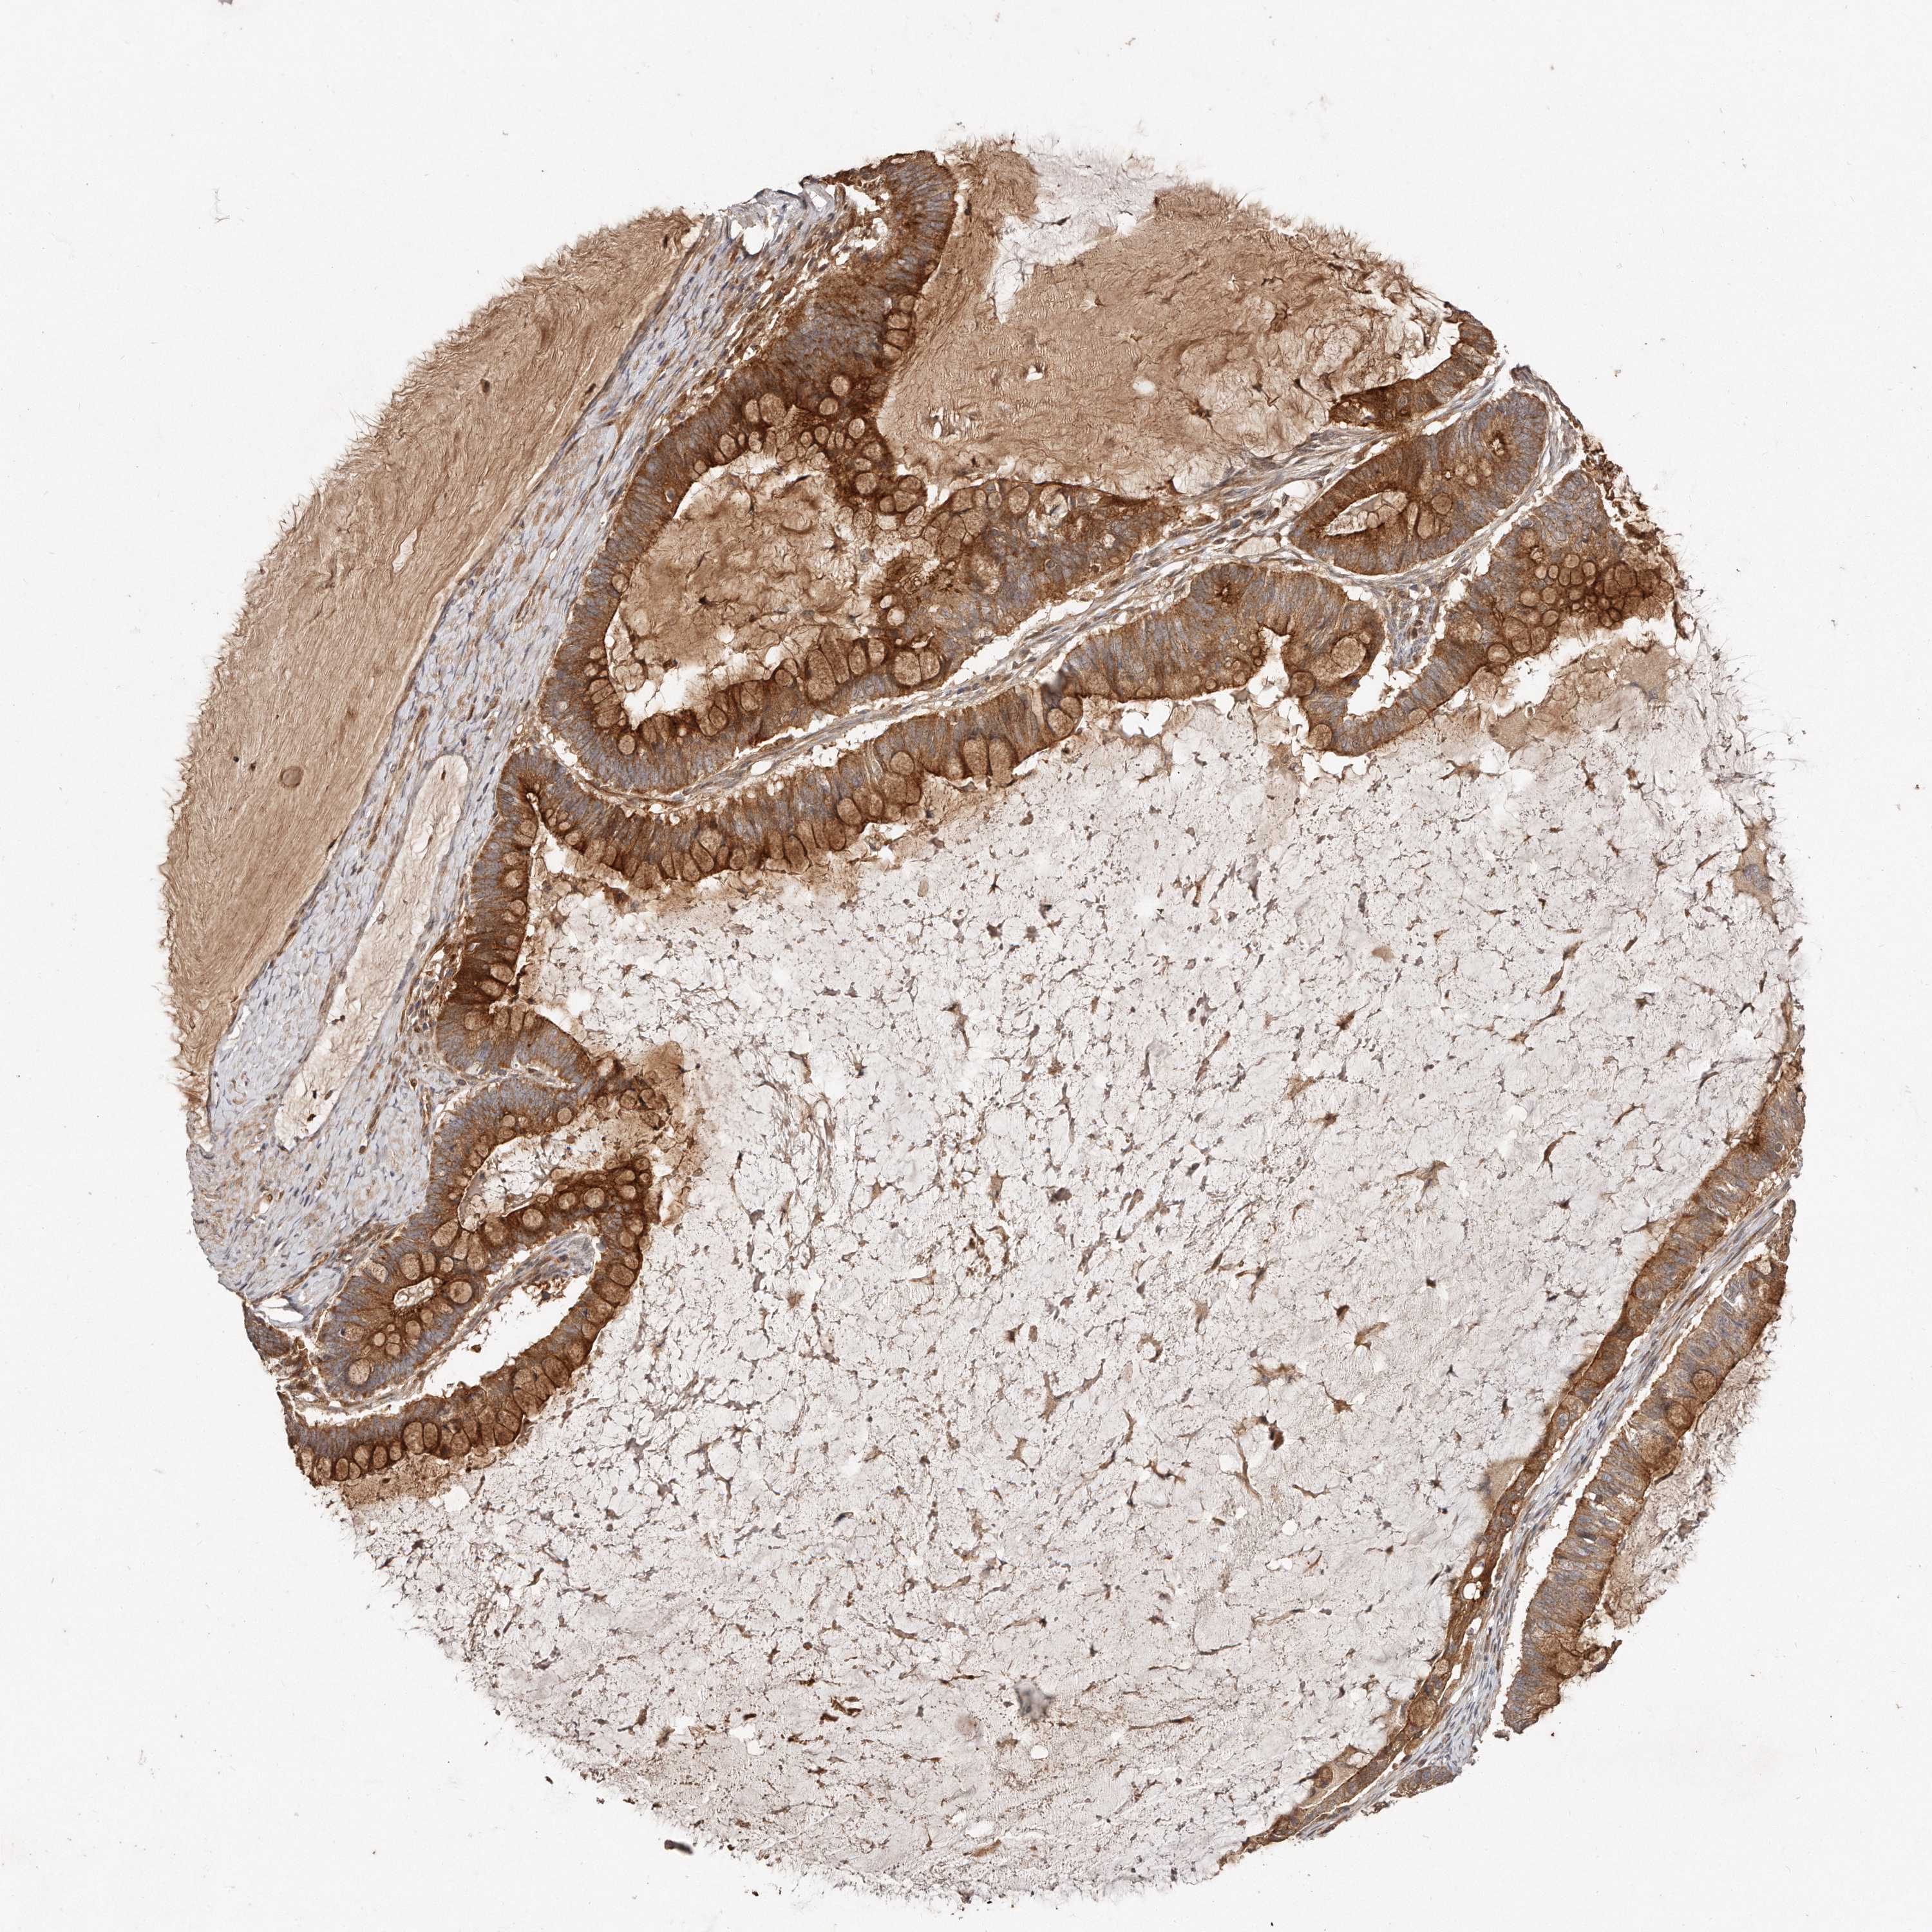

OVARIAN CANCER - Protein expressioni

A mouse-over function shows sample information and annotation data. Click on an image to view it in a full screen mode. Samples can be filtered based on level of antibody staining by selecting one or several of the following categories: high, medium, low and not detected. The assay and annotation is described here.

Note that samples used for immunohistochemistry by the Human Protein Atlas do not correspond to samples in the TCGA dataset.

Antibody stainingi

Antibody staining in the annotated cell types in the current human tissue is reported as not detected, low, medium, or high, based on conventional immunohistochemistry profiling in selected tissues. This score is based on the combination of the staining intensity and fraction of stained cells.

Each image is clickable and will lead to virtual microscopy that enables deeper exploration of all samples and also displays staining intensity scores, fraction scores and subcellular localization as well as patient and tissue information for each sample.

Antibody HPA030101

Staining

High

Medium

Low

Not detected

Intensity

Strong

Moderate

Weak

Negative

Quantity

>75%

75%-25%

<25%

None

Location

Nuclear

Cytoplasmic/membranous

Cytoplasmic/membranous,nuclear

Cystadenocarcinoma, serous, NOS

Carcinoma, endometroid

Cystadenocarcinoma, mucinous, NOS

Carcinoma, NOS